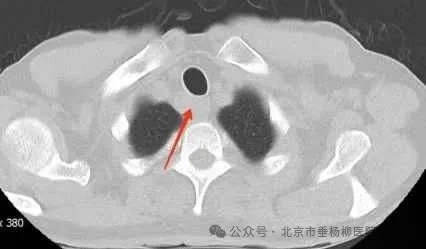

胸部CT(肺窗)

患者男性,60岁,主因“发现纵隔肿物9天余。”来诊。患者自述9天前因吞咽食物不适感查胸部增强CT,发现上纵隔气管右后方占位,大小约22*24mm,边界欠清,增强扫描不均匀强化,局部气管、食管受累,恶性待排,双肺及纵隔未见肿大淋巴结,未见胸腔积液,后完善胸部增强核磁:上纵隔气管右后方占位不均匀强化,局部气管、食管受累恶性病变待排,必要时穿刺活检;遂于当地医院依次行气管镜、胃镜检查,结果提示:气管上段右后侧壁外压型改变并管腔轻度狭窄;食管管腔通畅,未见异常隆起及异常外压改变,均未取到有效的病理结果。